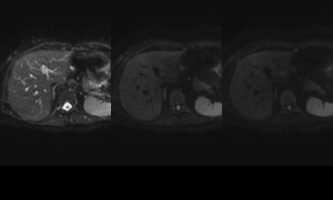

El estudio se complemento con resonancia magnética, donde se demostró la presencia de múltiples imágenes focales hepáticas confluentes con disminución de la señal en secuencias fuera de fase, no mostrando alteración de la señal en secuencias potenciadas en T2, sin signos de restricción al pulso difusión ni refuerzos anómalos luego de la administración de contraste endovenoso, estos hallazgos confirman la sospecha de esteatosis focal multinodular (fig. 5, 6 y 7).

En estos casos se recomienda realizar RM para confirmar la presencia de grasa en las “lesiones” identificadas y descartar otras etiologías, demostrando disminución de la señal en secuencias fuera de fase, sin alteración del pulso difusión (fig. 12 y 13).

Independiente de su patrón de presentación, no condicionan cambios del parénquima luego de la administración de contraste endovenoso, no obstante igualmente se utiliza el gadolinio como medio de contraste para descartar otras entidades que puedan simular esta patología. La TC no suele aportar datos concluyentes cuando los focos de esteatosis son de pequeño tamaño y de bajo contenido graso, no logrando una adecuada diferenciación en su atenuación.7-8 (fig. 14)